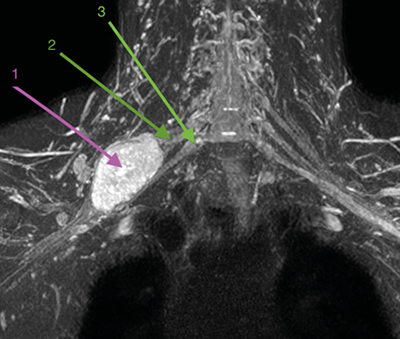

Con la orientación diagnóstica inicial de schwannoma de plexo braquial derecho con escasa repercusión clínica, se decidió actitud expectante. Se instauró tratamiento analgésico de primer escalón y ansiólisis a demanda para dormir. El paciente era reticente al tratamiento neuromodulador debido a sus efectos secundarios. Seis meses después, tras una nueva RM de control, se observó un discreto crecimiento de la lesión con probable efecto compresivo por los músculos escalenos anterior y medio (Figuras 1 y 2). Se indicó una infiltración diagnóstico-terapéutica con toxina botulínica tipo A (Botox®) ecodirigida. Las crisis de dolor eran más frecuentes y de más minutos de duración y empezaban a afectar su calidad de vida. EVA 2-3 en reposo, 8-9/10 en las crisis.

Fig. 2. RM coronal en STIR. 1. Schwannoma de plexo braquial derecho. 2. Tronco medio del plexo braquial. 3. Tronco inferior del plexo braquial